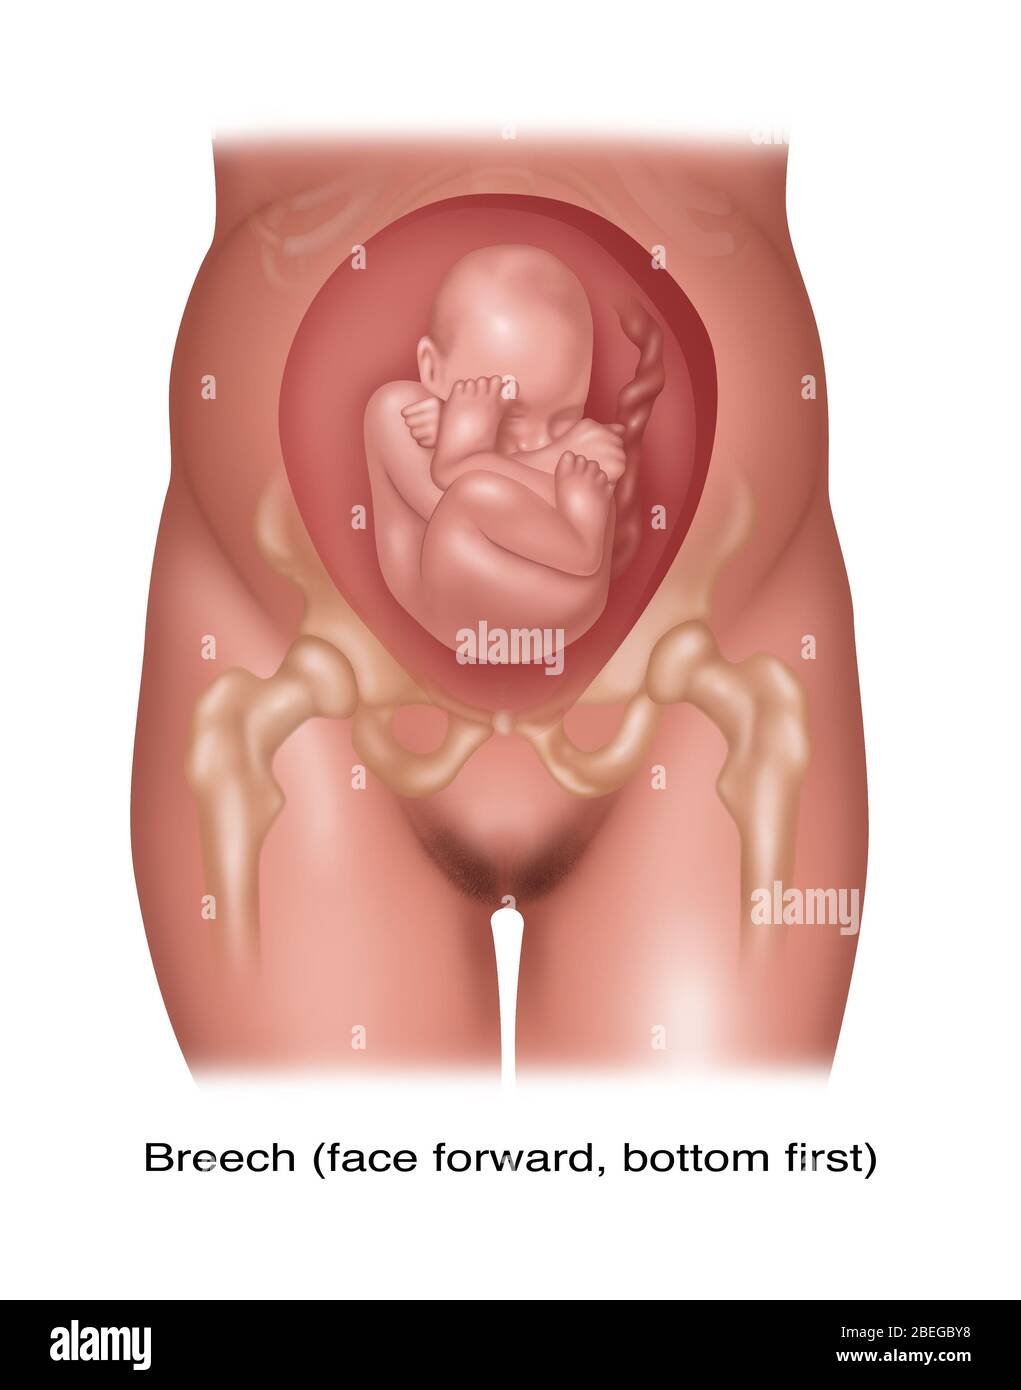

Fetus Positions in Uterus, Illustration Stock Photohttps://www.alamy.com/image-license-details/?v=1https://www.alamy.com/fetus-positions-in-uterus-illustration-image353173031.html

Fetus Positions in Uterus, Illustration Stock Photohttps://www.alamy.com/image-license-details/?v=1https://www.alamy.com/fetus-positions-in-uterus-illustration-image353173031.htmlRF2BEGBPF–Fetus Positions in Uterus, Illustration

Fetus Positions in Uterus, Illustration Stock Photohttps://www.alamy.com/image-license-details/?v=1https://www.alamy.com/fetus-positions-in-uterus-illustration-image353173074.html

Fetus Positions in Uterus, Illustration Stock Photohttps://www.alamy.com/image-license-details/?v=1https://www.alamy.com/fetus-positions-in-uterus-illustration-image353173074.htmlRF2BEGBT2–Fetus Positions in Uterus, Illustration